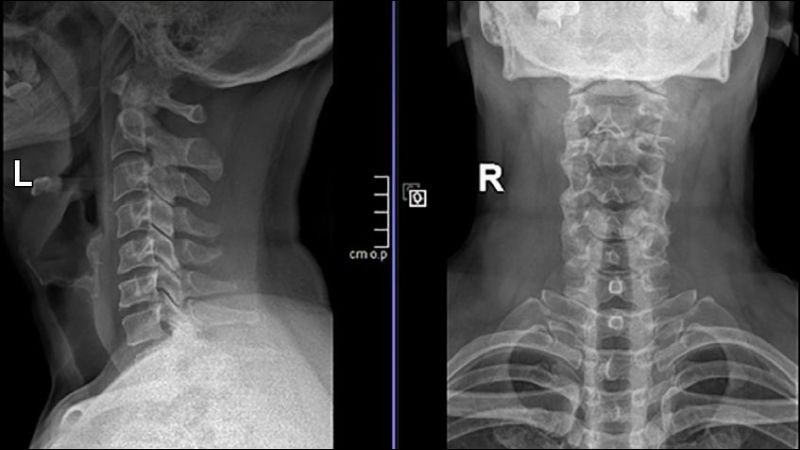

Các kỹ thuật chẩn đoán hình ảnh thường ít được chỉ định để chẩn đoán nguyên nhân đau cổ trừ khi người bệnh đến khám vì đau cổ sau chấn thương hoặc đau cổ dữ dội không cải thiện sau lần khám và điều trị trước đó. Các phương pháp chẩn đoán hình ảnh có thể được chỉ định, bao gồm:

- X-quang: là kỹ thuật phổ biến để phát hiện các bất thường về xương ở đốt sống cổ như gãy xương, cong vẹo cột sống, thoát vị đĩa đệm.

X-quang có thể giúp phát hiện các bất thường về xương